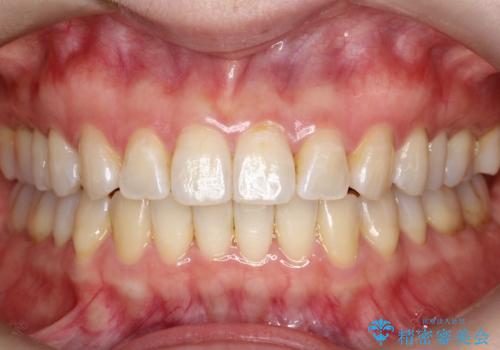

【インビザライン 】前歯の凸凹をなおしたい

- 前歯の凸凹を主訴に来院されました。

インビザライン にて治療を行い、歯並びが綺麗になったと満足していただきました。

前歯のガタガタの量が多かったため、IPR(歯のサイズを小さくするための処置)を行なって治療しました。